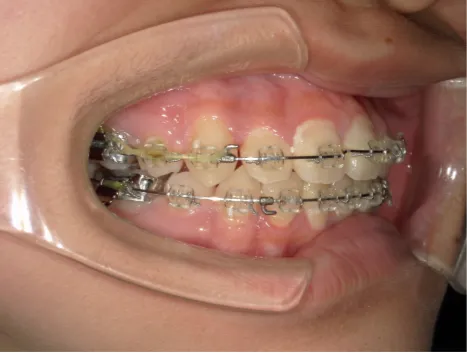

治療中⑧高1:15y11m 抜歯治療中

治療中⑨高2:17y1m 抜歯治療中

治療後⑩高2:17y7m 抜歯治療終了